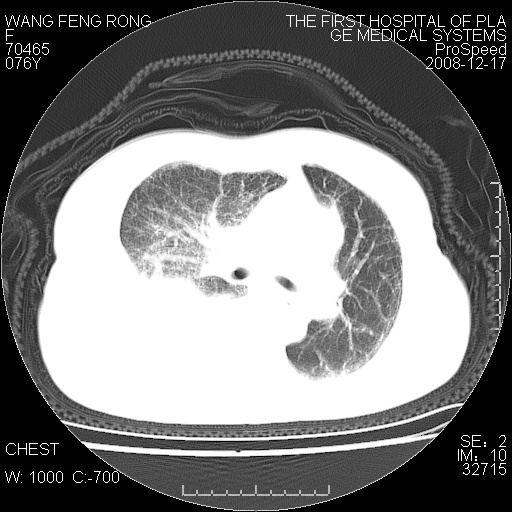

右侧胸腔积液,致右肺膨胀不全,双肺间质纤维化改变

右侧胸腔积液,致右肺膨胀不全,双肺间质纤维化改变!建议抽液后化验!

1)考虑两肺炎症感染;不排除肺泡癌可能。2)两肺间质纤维化。3)右侧胸腔积液。

右侧胸腔积液,右肺膨胀不全伴感染(不除外肺癌),双肺间质水肿

右肺大部实变,其内可见支气管影,但分支减少,宽窄不均,走行僵直,同侧胸腔大量积液;纵隔内见多发淋巴结影,但淋巴结大部有钙化;主动脉壁钙化;临床上病人咳嗽、消瘦。所以我考虑:1、结核(依据:右下肺实变,纵隔内淋巴结符合结核表现,同侧并发胸膜炎表现);2、支气管肺泡癌(依据:实变的肺组织内支气管分支减少,宽窄不均,走行僵直,没有把它放在第一诊断是因为没有看到明显肿大的淋巴结);3、动脉硬化(主动脉壁钙化就支持这个诊断)。

病理结果,肺泡癌